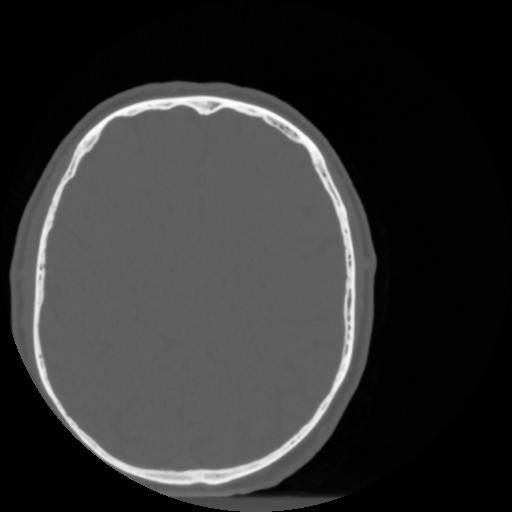

4 CEREBRO,,Vol,0.5,CEREBRO,,